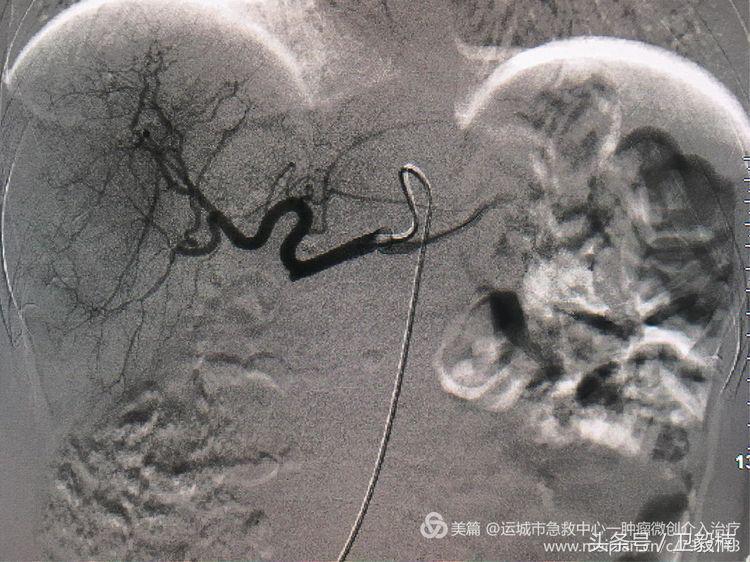

为解决腹痛及控制转移瘤来我院行介入治疗。

经过肿瘤的供血动脉给肿瘤灌注高浓度的化疗药,杀灭肿瘤细胞,再给注入栓塞剂,让肿瘤缺血坏死。达到饿死肿瘤的目的